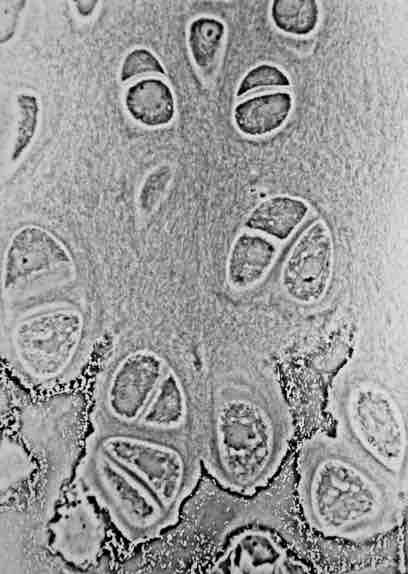

Hyaline cartilage showing chondrocytes and organelles, lacunae and matrix.

This is a microscope slide of hyaline cartilage, showing its chondrocytes and organelles, lacunae and matrix.